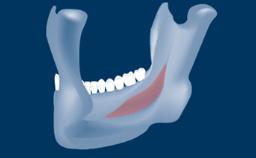

In this short microlearning module on digitally guided sinus floor elevation, we delve into a specialized aspect of the digital workflow for implant-guided surgery, focusing on the use of digital guides in the sinus floor elevation technique.

- describe the indications for digital guides in SFE